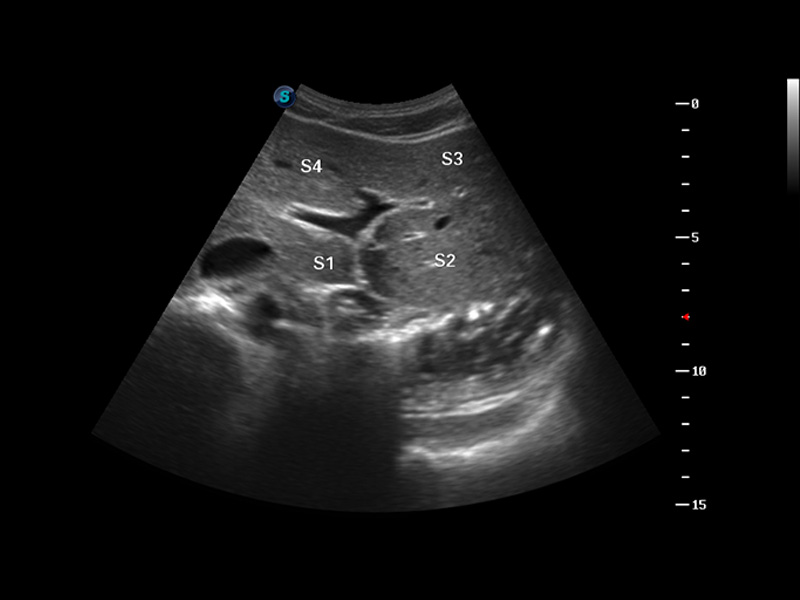

临床图

肝脏